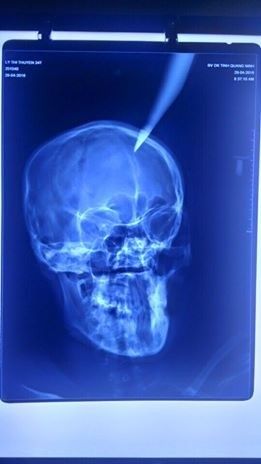

Kết quả chụp X-quang cho thấy phần đầu nhọn của dao cắm sâu 4 cm vào não. Theo người nhà bệnh nhân, vụ tai nạn hi hữu xảy ra khi bố chồng của chị T. sửa mái nhà đã vô tình làm rơi con dao dắt trong người xuống, cắm thẳng vào đầu con dâu đang đi qua ở phía dưới.